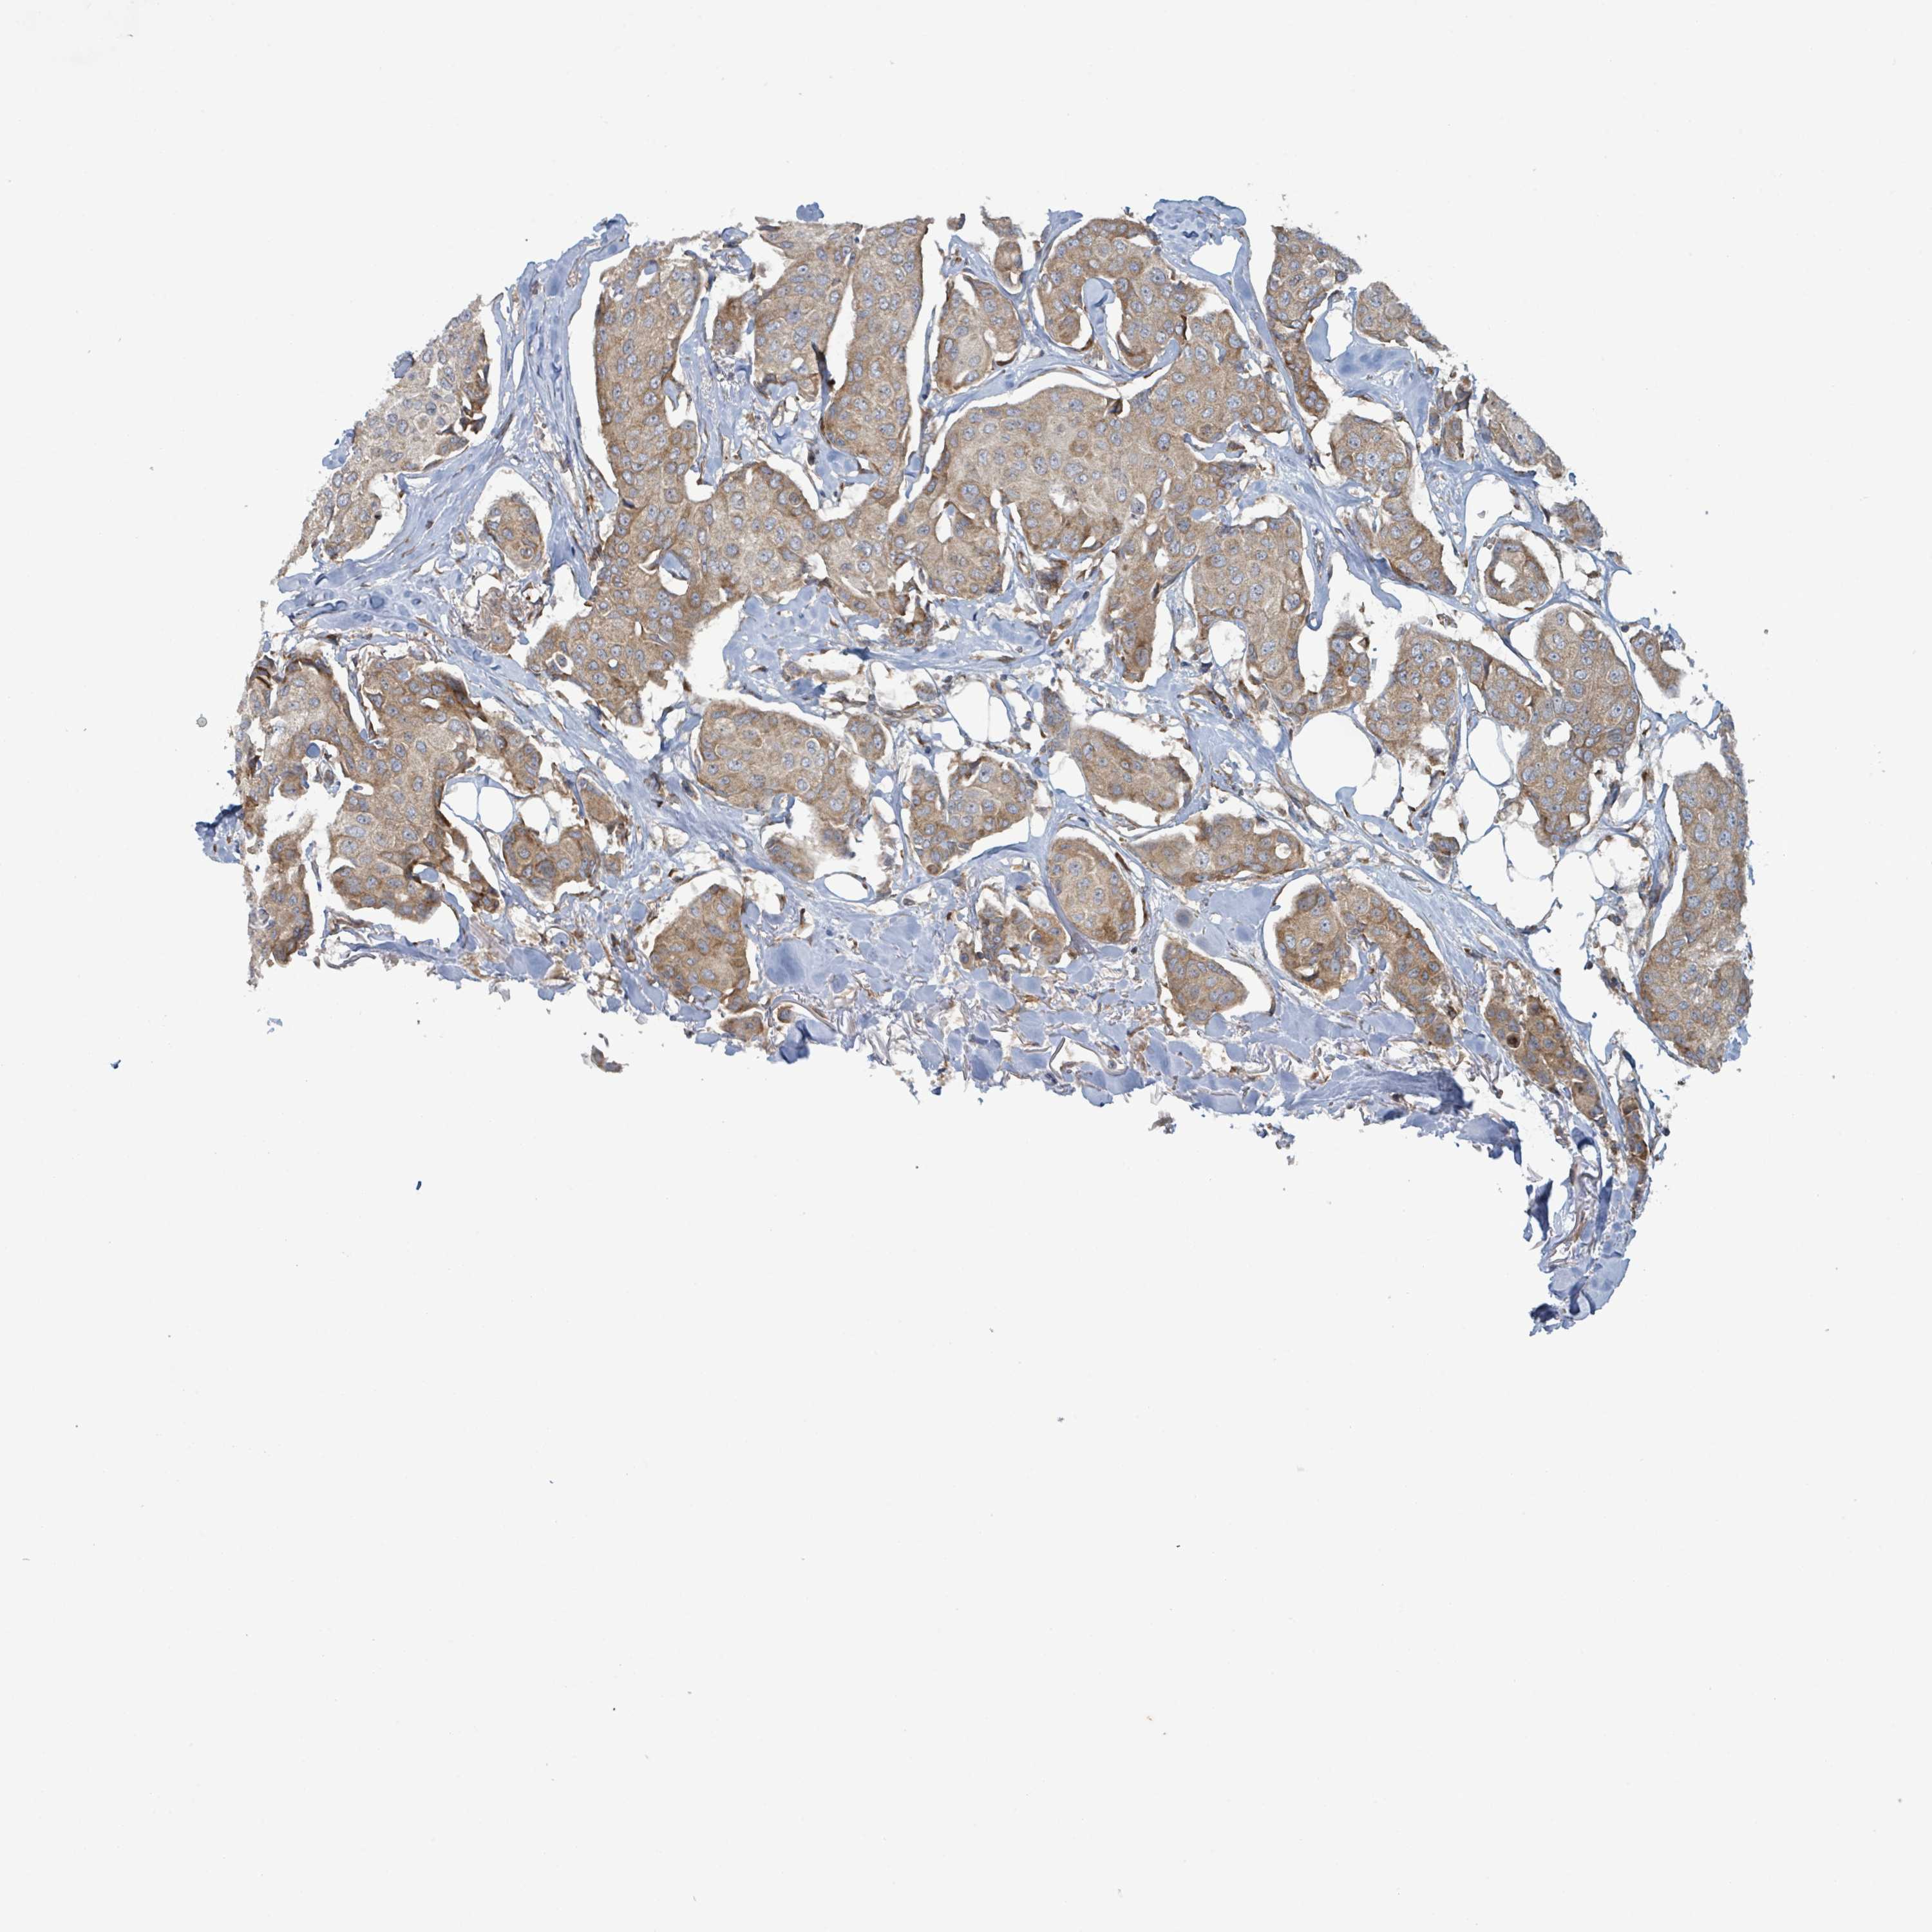

BRCA TCGA BRCA VALIDATION PROTEIN EXPRESSION

Breast cancer

Human cancer